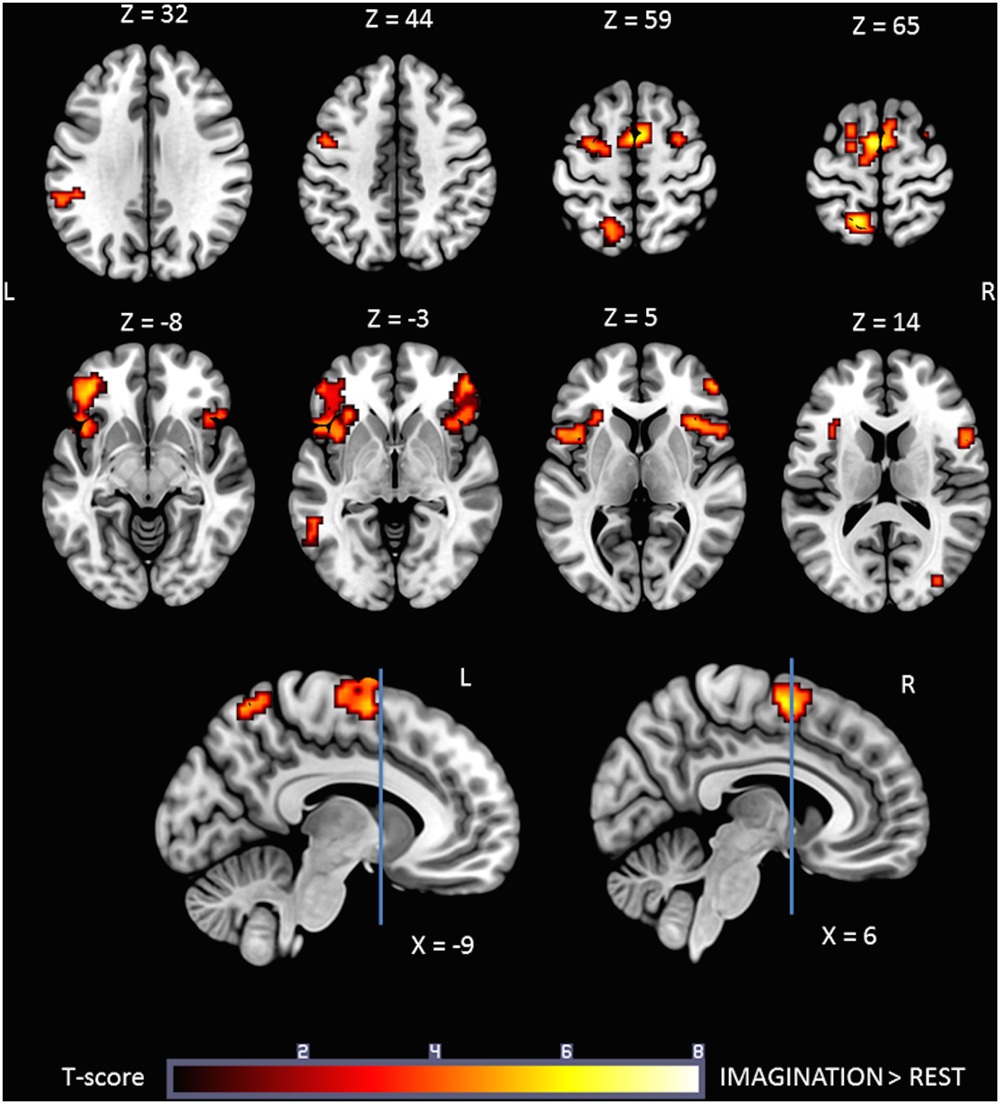

Figure 3 shows the statistical parametric map for the IMAGINATION > REST contrast, which represents brain activity during the imagined gait task. Bilateral clusters in the frontal inferior gyrus and anterior insula were dominant. The foremost part of these clusters relates to the ventrolateral prefrontal cortex (BA 44, 45, and 47). Active voxels were also located in motor-related areas such as SMA (R and L; BA = 6) and the dorsal premotor cortex (R and L, BA = 6). More precisely, activations concerned the SMA-proper (R and L) and the pre-SMA (R). Finally, additional clusters were found in the Middle Temporal Gyrus (L), Middle Occipital Gyrus (R), SupraMarginal Gyrus (L) and Precuneus/Parietal Sup (L). Details regarding location are provided in Table 2.

FIGURE 3

Statistical parametric map for the IMAGINATION > REST contrast p-value threshold of <0.05 FDR-corrected at voxel level with a minimum cluster extent of ten contiguous voxels; images are presented according to neurological convention (R = right, L = left). Blue lines in the sagittal images represent the vertical plane passing through the anterior commissure, separating pre-SMA (anteriorly) and SMA proper (posteriorly). See text for details.